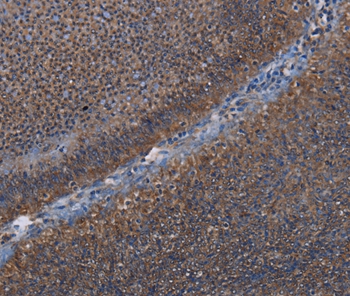

Immunohistochemical analysis of paraffin-embedded Human rectal cancer tissue using #36584 at dilution 1/50.